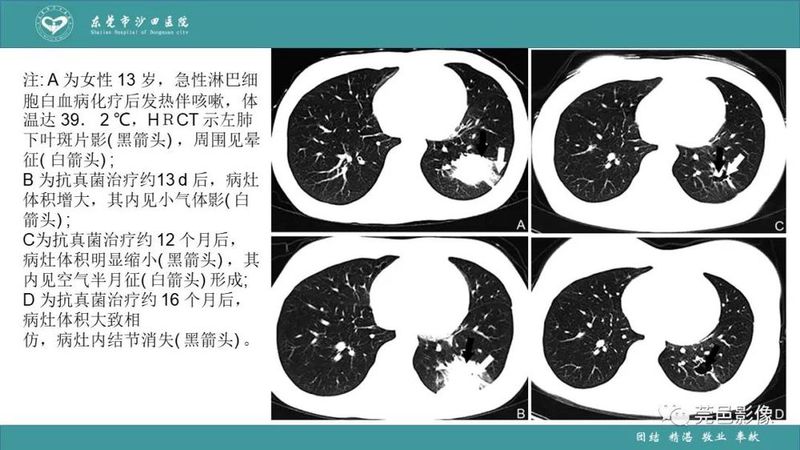

「肺炎克雷伯杆菌肺炎」影像学诊断+鉴别诊断